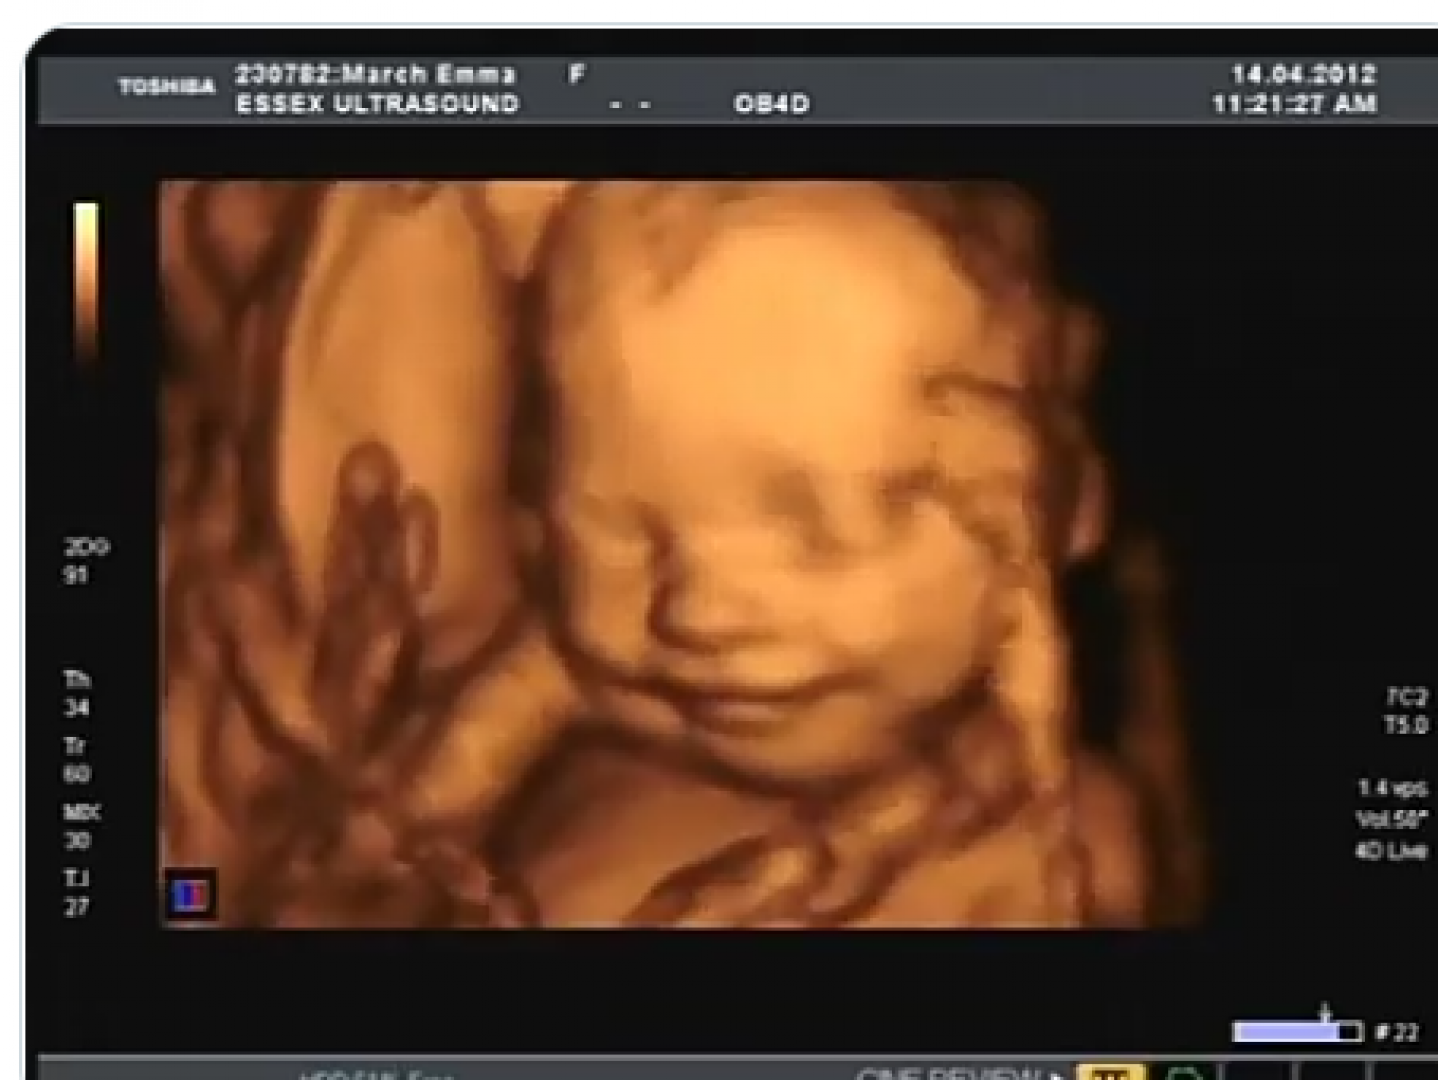

حركة الجنين من أهم العلامات التي تشير إلى صحة وسلامة الجنين بشكل عام، كما أن حركة الجنين في الشهر التاسع تقل من حيث الكثافة ولكنها تزداد من حيث القوة، مما يسبب الآلام الشديدة للأم لفترات طويلة.

قد تتسبب قلة الحركة للأم في القلق والتوتر إلا أنها من الأشياء الطبيعية ما لم تقل عن المعدل الطبيعي للحركة، حيث تكون حركة الجنين خلال الشهر التاسع بشكل عام 10 ركلات لكل ساعتين، وهذا لا يعتمد في حالات الولادة فقد تقل أو تزداد الحركات حسب حالة الأم والطفل عند الولادة.